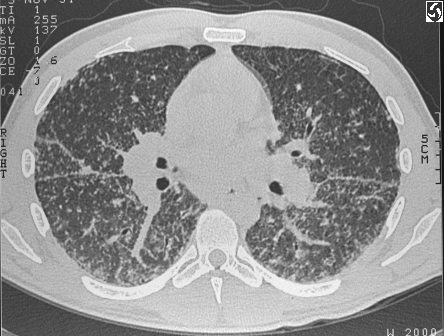

HRCT Interstial Lung Disease

Sarcoidosis

HRCT Fx:

Common Findings

Uncommon findings: